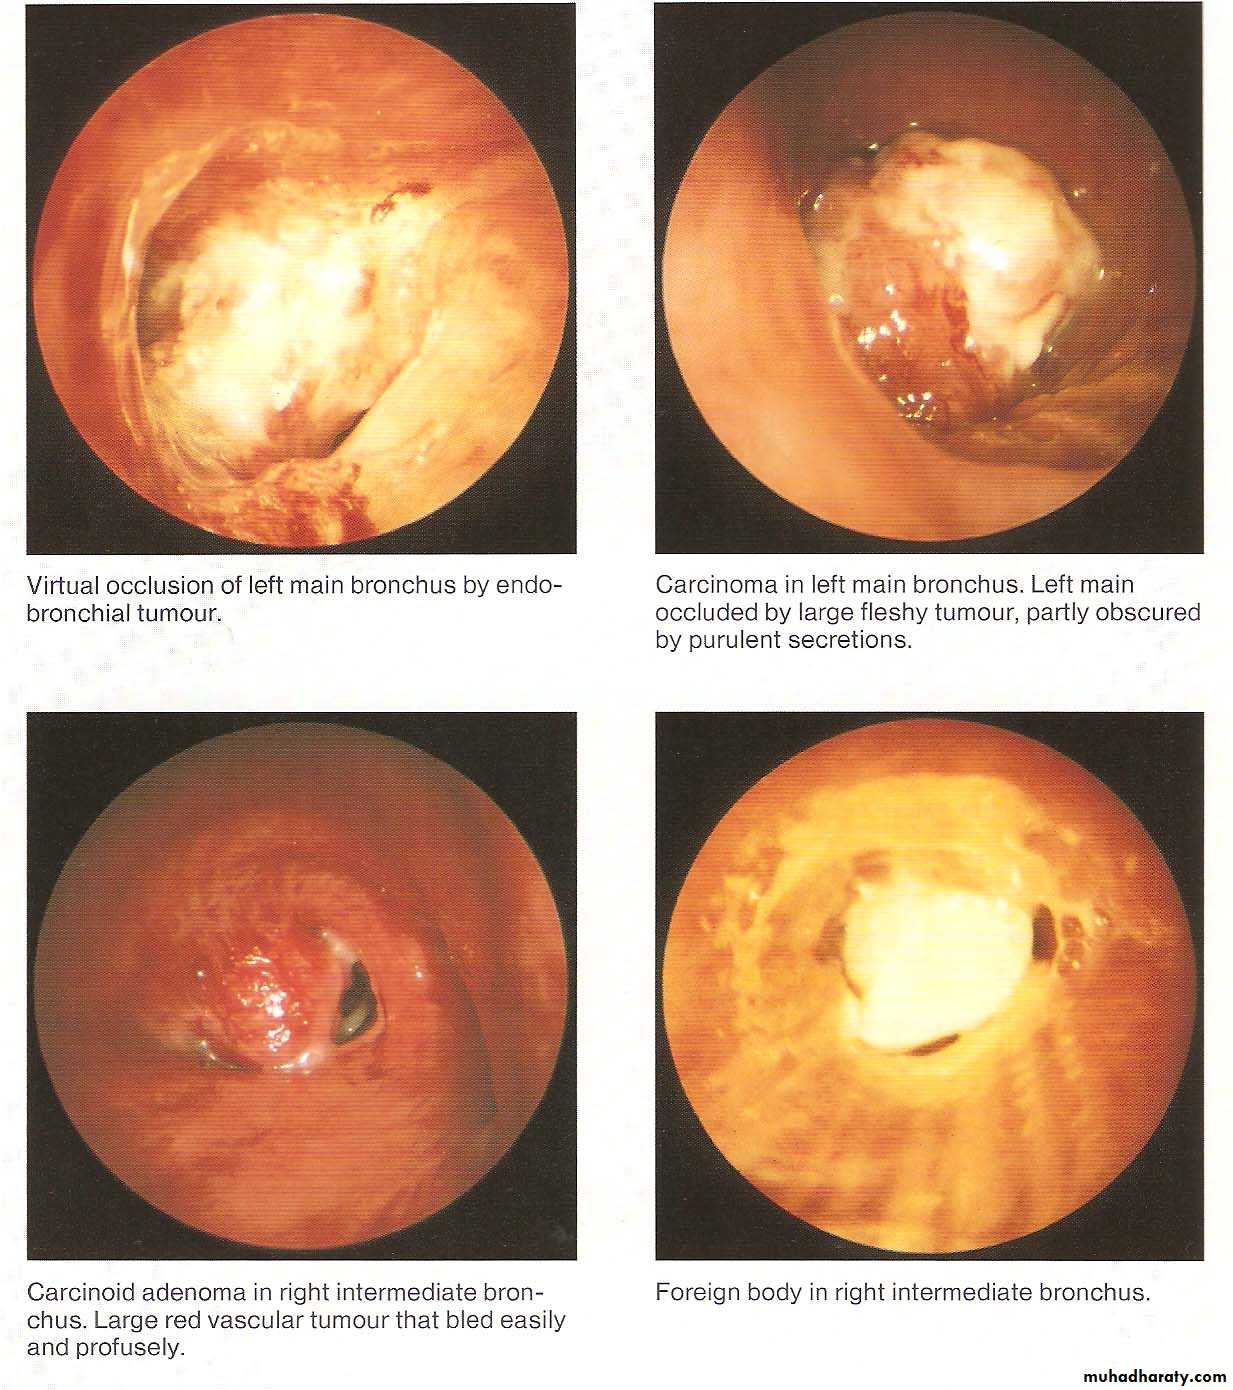

• Normal Bronchoscopic Findings

• Abnormal Bronchoscopic Findings

Bronchial Carcinoid Tumors

Resemble intestinal carcinoid as the cytoplasm as the cytoplasm of their cells contains neurosecretory granules .In the bronchus these tumors arise from the neuro endocrine argentafin cells of bronchial mucosa (Kultchitsky ‘s cells ) .They are grouped among APUD tumors (Amine Percursor Uptake Decaboxylation) .

They are capable of producing a number of hormones like Serotonin , histamine and gastrin .They are slowly growing tumors , but sometime they are aggresaive termed (atypical carcinoid ) .They present with cough , haemoptysis and dyspnea ) .

Carcinoid Syndrome is a rare ,presents with episodes of flushing , diarrhea and in addition to the systemic manifestations ,there may be cardiac manifestations .Elavated 5-HIAA may be detected in the urine ,which may be diagnostic .Bronchoscopic appearance is diagnostic and severe bleeding may follow a biopsy .Surgical excision is the treatment of choice .